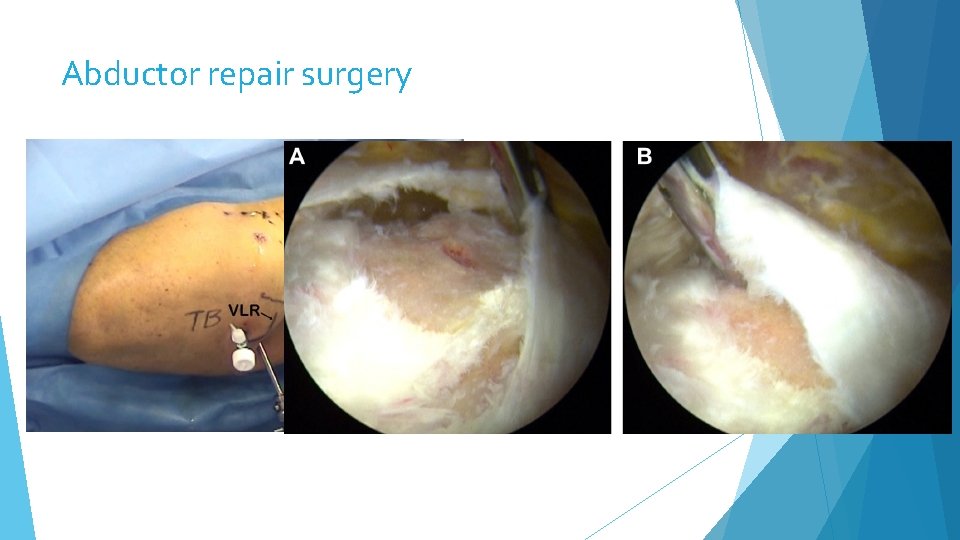

Abductor repair surgery

Specialties Hip: Hip Labral repair, FAI surgery, Arthroscopic Hip Abductor Repair NEW to Sorry! Not hip replacement Shoulder: Rotator Cuff Repair, Labral Repair, Subpectoral Biceps Tenodesis, Shoulder Stabilization Knee: Anatomic ACL Reconstruction, All-Inside Meniscus Repair, Cartilage Repair and Restoration, Patella Stabilization with MPFL Reconstruction Elbow: Elbow Arthroscopy, UCL Reconstruction (Tommy John Procedure), Distal Biceps Repair